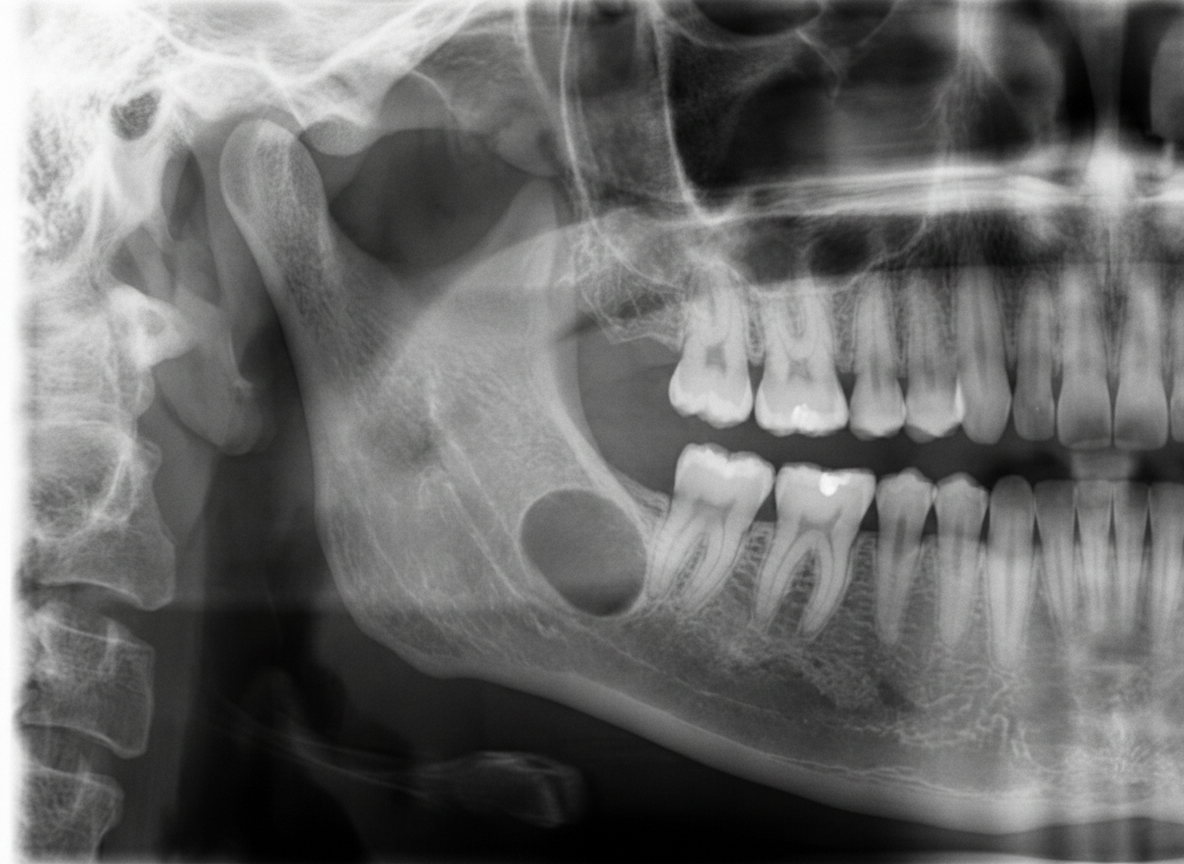

A 45-year-old male presented for a routine dental checkup. All teeth in the lower right quadrant were vital. A panoramic radiograph was taken. Which of the following can be the most probable diagnosis?

Explanation: ***Stafne bone cyst*** - **Stafne bone cyst** is an **asymptomatic radiolucent lesion** typically found **below the inferior alveolar canal** in the **posterior mandible** of middle-aged males during routine radiographic examination. - The **vital teeth** in the affected quadrant strongly support this diagnosis, as Stafne cysts are **developmental defects** containing **salivary gland tissue** and do not affect tooth vitality. *Dentigerous cyst* - **Dentigerous cysts** are associated with the **crown of an unerupted tooth**, typically **third molars** or **canines**. - They present as **unilocular radiolucencies** surrounding the **crown** of an impacted tooth, which is not described in this case. *Radicular cyst* - **Radicular cysts** arise from **chronic periapical inflammation** and are associated with **non-vital teeth** with **pulpal necrosis**. - Since all teeth in the lower right quadrant are **vital**, this diagnosis is ruled out as radicular cysts require **endodontic infection**. *Calcifying odontogenic cyst* - **Calcifying odontogenic cyst** (Gorlin cyst) typically presents as a **mixed radiolucent-radiopaque lesion** with **calcifications**. - It commonly occurs in the **anterior maxilla** and shows **calcific deposits** on radiographs, unlike the presumed **radiolucent lesion** in the posterior mandible.